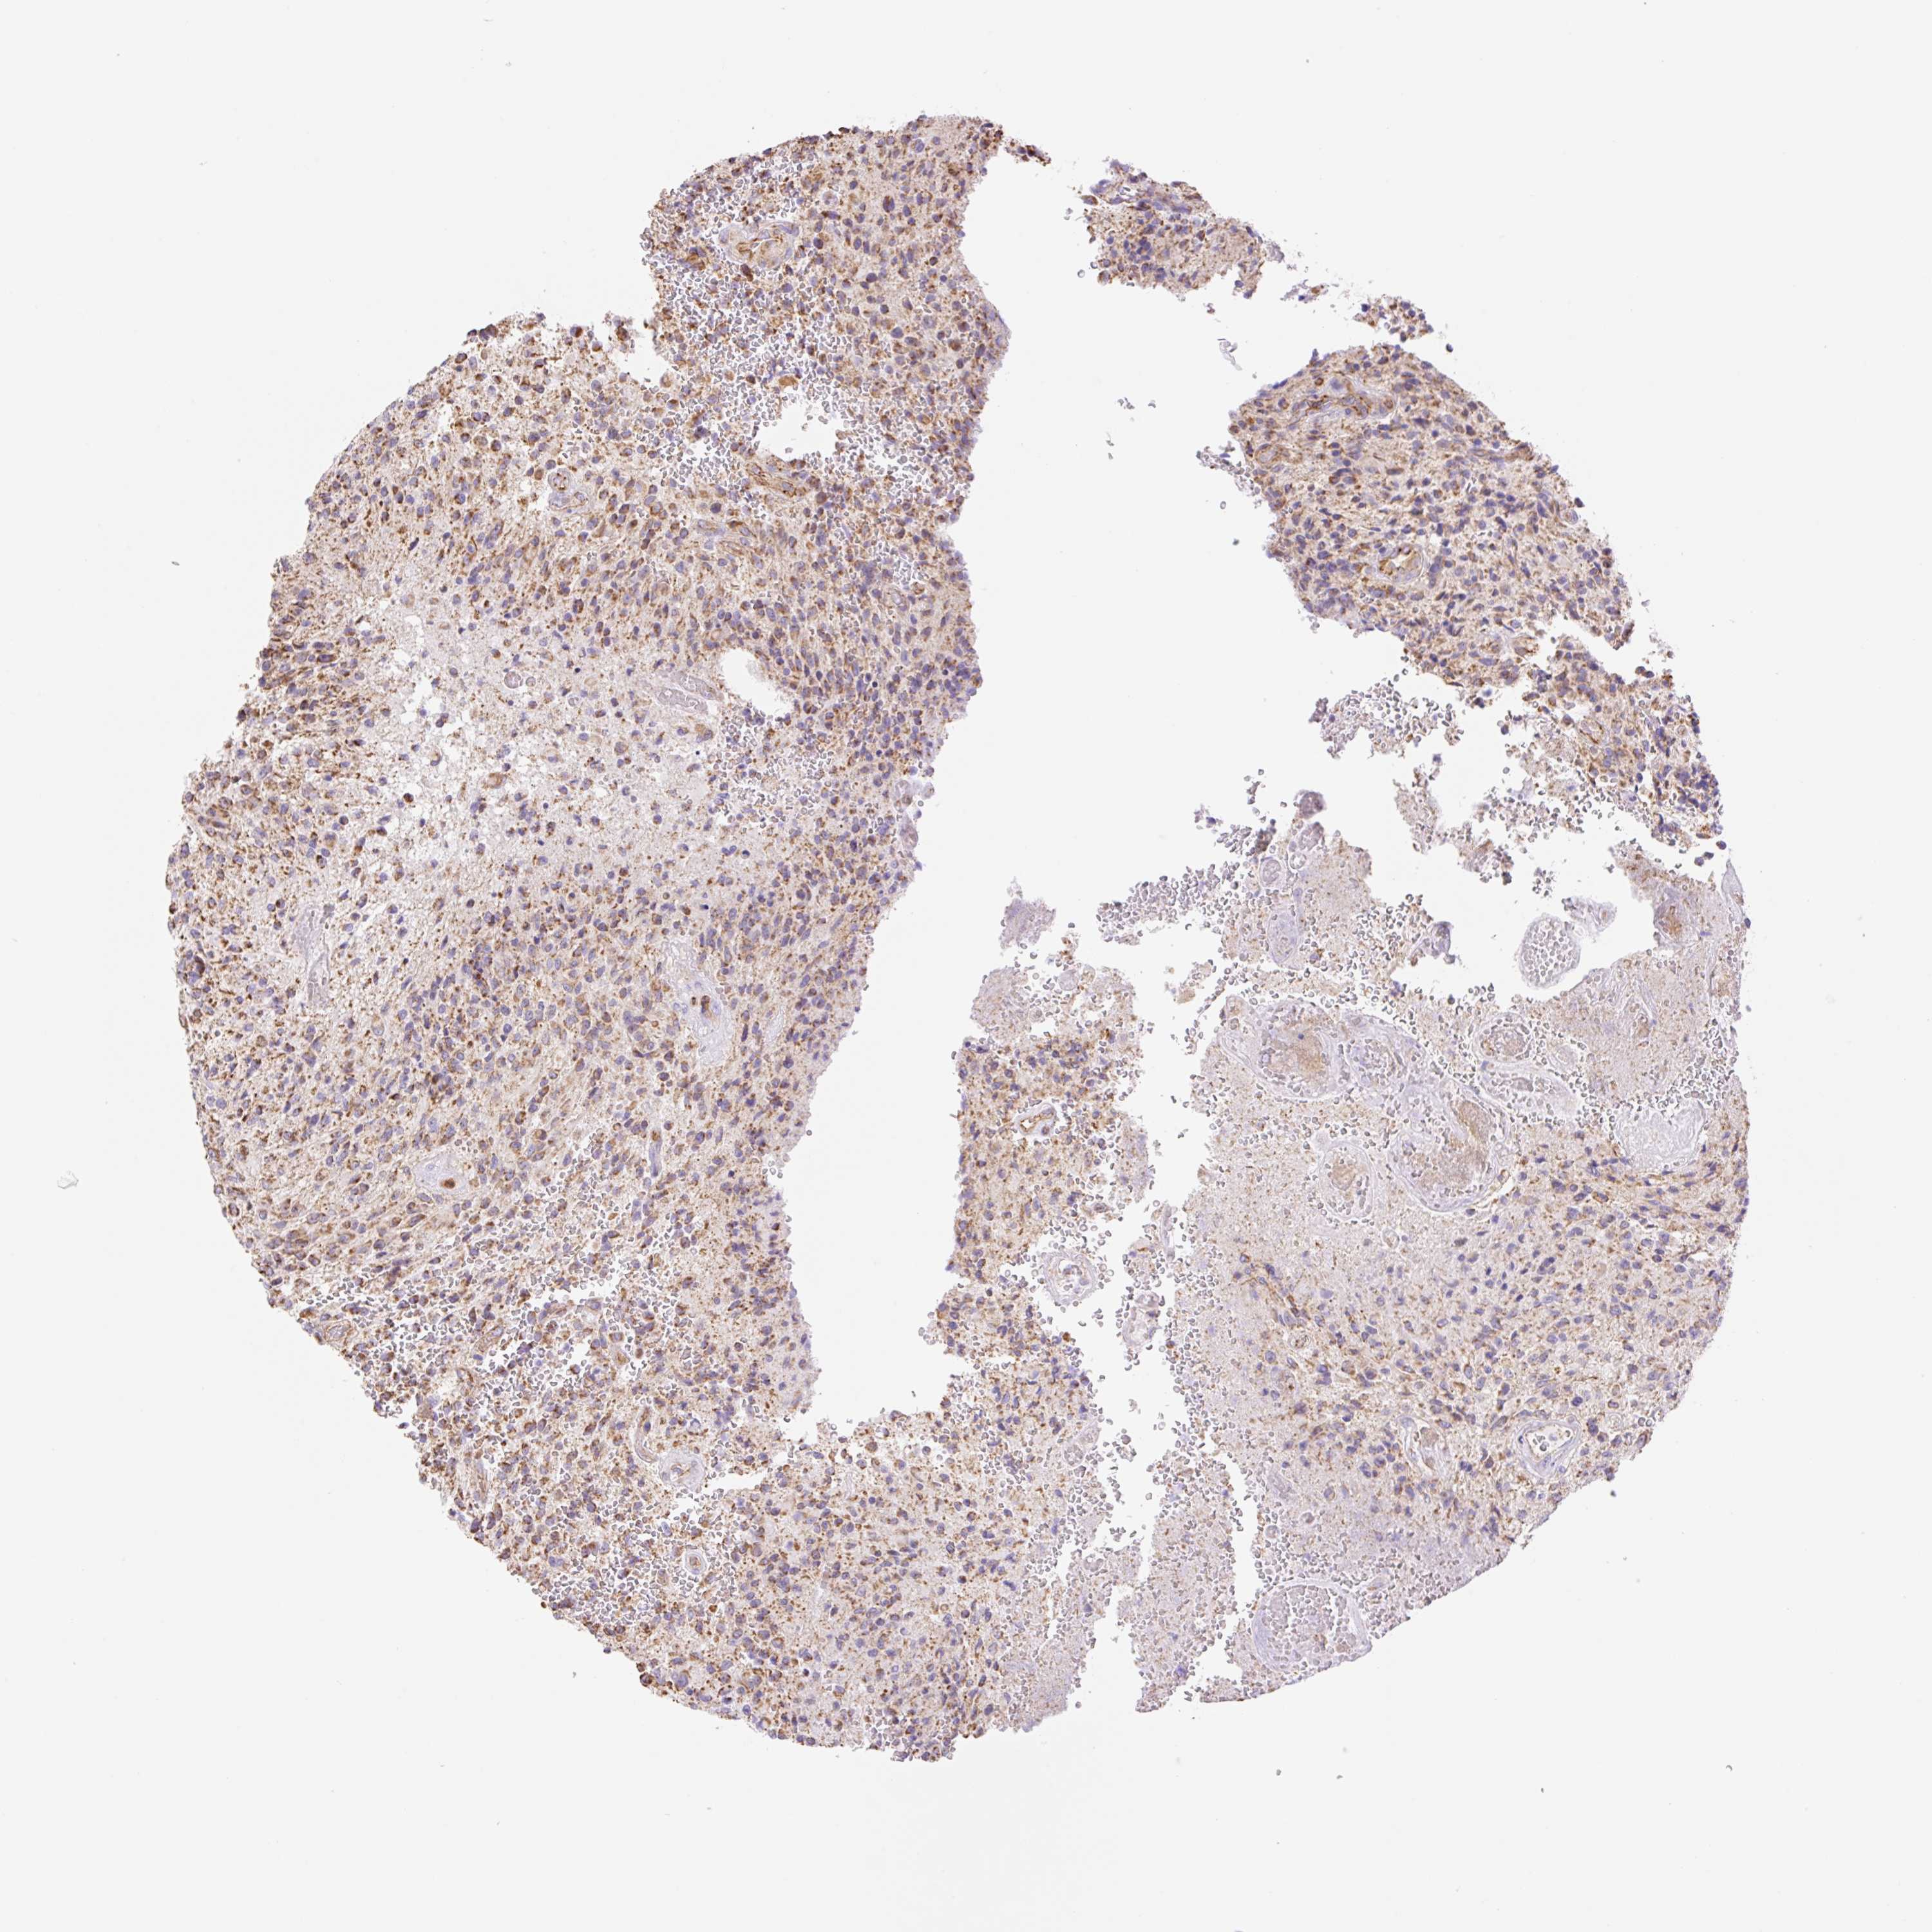

GLIOMA - Protein expressioni

A mouse-over function shows sample information and annotation data. Click on an image to view it in a full screen mode. Samples can be filtered based on level of antibody staining by selecting one or several of the following categories: high, medium, low and not detected. The assay and annotation is described here.

Note that samples used for immunohistochemistry by the Human Protein Atlas do not correspond to samples in the TCGA dataset.

Antibody stainingi

Antibody staining in the annotated cell types in the current human tissue is reported as not detected, low, medium, or high, based on conventional immunohistochemistry profiling in selected tissues. This score is based on the combination of the staining intensity and fraction of stained cells.

Each image is clickable and will lead to virtual microscopy that enables deeper exploration of all samples and also displays staining intensity scores, fraction scores and subcellular localization as well as patient and tissue information for each sample.

Antibody HPA056293

Staining

High

Medium

Low

Not detected

Intensity

Strong

Moderate

Weak

Negative

Quantity

>75%

75%-25%

<25%

None

Location

Nuclear

Cytoplasmic/membranous

Cytoplasmic/membranous,nuclear

Glioma, malignant, High grade